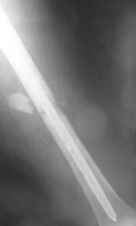

Консультировал рентгенограммы после интрамедуллярного остеосинтеза бедра гвоздем Fixion. Пациенту объяснили, что важнее сохранить перелом "закрытым" чем фиксировать осколок из дополнительного разреза. Сами собираемся оперировать голень и думаем, что без "открытия" места перелома не обойтись.